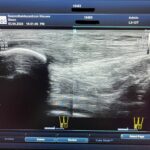

Echografie is een beeldvormend onderzoek naast het lichamelijk onderzoek waarbij wij als fysiotherapeut een beeld krijg van het weefsel onderhuids tot aan de bot lijn. De botten kunnen wij niet beoordelen daarvoor moet uitsluitend een röntgenfoto voor gemaakt worden.

Door middel van geluidsgolven van het echoapparaat het lichaam doordringen en reflecteren tussen zachte en harde oppervlakken.